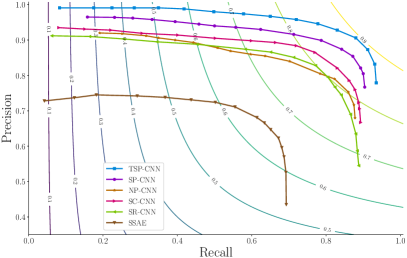

As is common, the threshold value is varied to generate a Precision-Recall curve. The Precision-Recall curve for averaged values over all images in the test set from UW Dataset [5] is plotted in Fig. 11, and for PSU Dataset the PR-curve is plotted in Fig. 12. For consistency, results for UW Dataset for the proposed SP-CNN and TSP-CNN are based on using the same assessment procedure as in [5], which used a split of training vs. test images (using the official assessment source codes of [5] provided by the paper’s author). For PSU Dataset, a split of training vs. test images was employed by all competing methods. Fig. 11 essentially compares SP-CNN and TSP-CNN against state of the art deep learning methods: 1.) SC-CNN [5], 2.) SR-CNN [16], 3.) SSAE [49], 4.) CSP-CNN [19] and two other popular feature and morphology based methods 5.) LIPSyM [7], and 6.) CRImage [30].

In the case of UW Dataset, and results for the aforementioned competing methods are obtained directly from comparisons already reported in [5, 19]. Figures 11 and 12 reveal that SP-CNN and TSP-CNN achieve Precision-Recall curves that outperform state of the art alternatives. To obtain a single representative figure of merit for each method, we chose the threshold value, , which maximizes the F1-score correspondingly for each method. These ‘best F1-scores’ for each method are then reported in Table III for the UW Dataset [5]. In Table IV, ‘best F1-scores’ are reported for the PSU Dataset. Note that in Table IV and Fig. 12, we focus on deep learning methods only because: 1.) they are shown to comfortably outperform traditional feature and morphology based methods and 2.) the particular methods in [7, 30] employ features that are not really appropriate for the PSU dataset leading to vastly degraded results. Further, comparisons with CSP-CNN [19] are not reported for the PSU dataset because CSP-CNN is highly customized for the UW dataset.

To show the value of prior guided regularization, we also report in Tables III and IV, the results of our network for the case with in Eq. (9). Because no regularizers are involved, we call this – No Prior CNN (NP-CNN). The case with only will reduce Eq. (9) to Eq. (3) and hence corresponds to SP-CNN. Consistent with SP-CNN, the aforementioned NP-CNN also uses layers. The quantitative gains of using shape priors and learning shapes, i.e. (T)SP-CNN vs. NP-CNN are readily apparent in Tables III and IV. Similar trends can also be seen in Figs. 11 and 12 in terms of the benefits of shape priors.